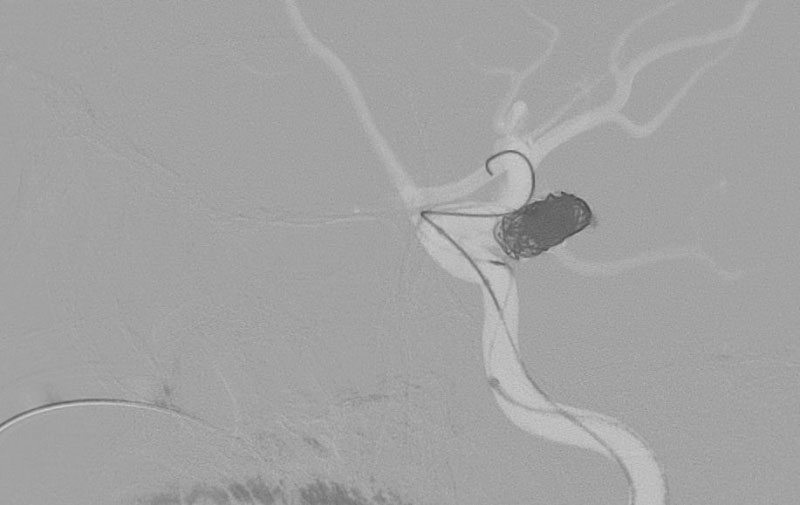

No.1596 手術中